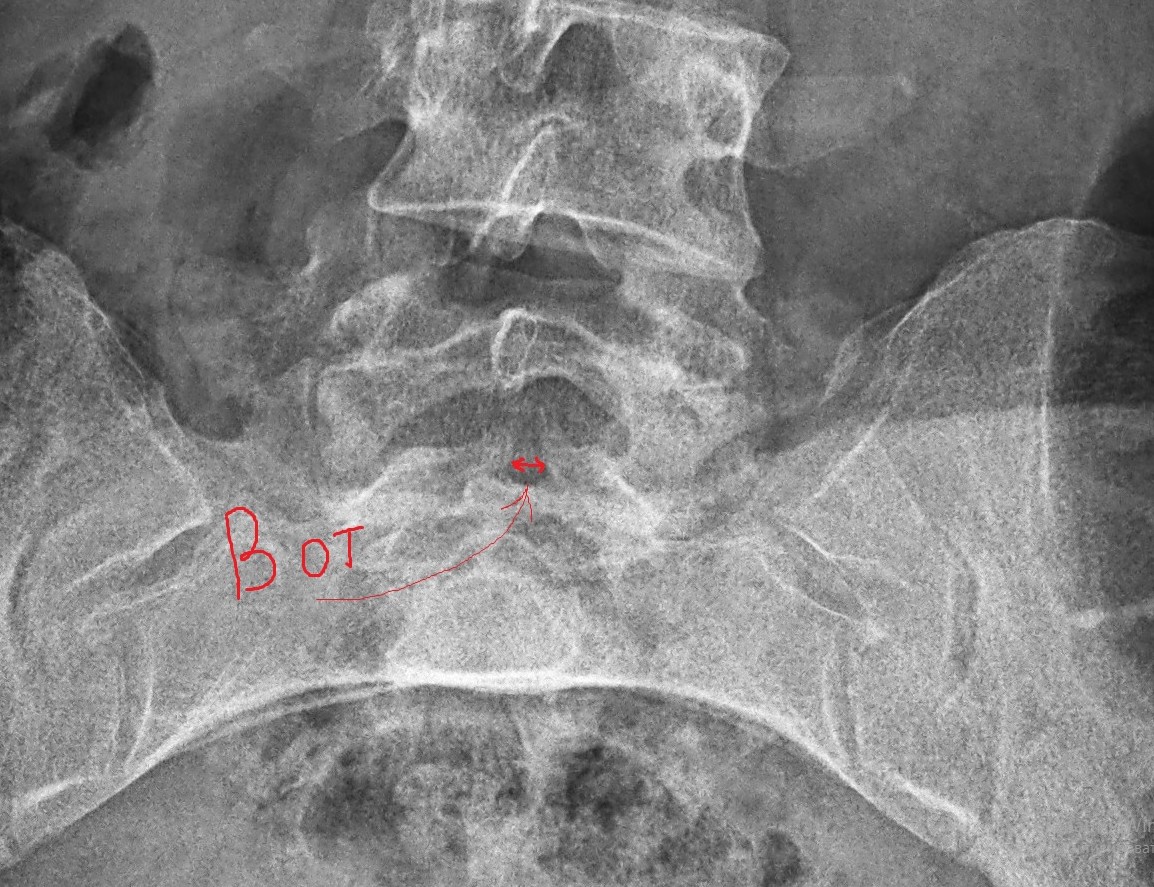

Рентген шейных позвонков при спина бифида

Раздел: Фотозарисовки